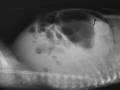

Hemorragia adrenal em recém nascido

Set de 2024.